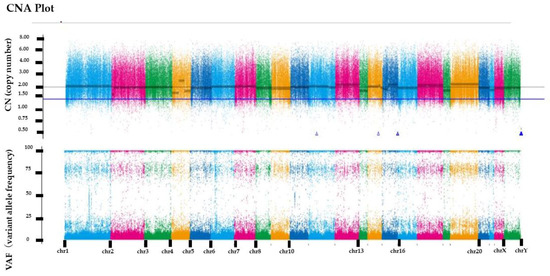

RecQ like heliccase4 (RECQL4), CNTNAP2, and PRDM2 variants, which are tumor suppressor genes, were detected by whole-exome sequencing. All three variants were germline variants and revealed a somatic uniparental disomy (somatic UPD). Variant positions and variant allele frequencies are shown in Table 1. However, no actionable variants and no copy number alterations were identified in the known oncogenes. The copy number plot was normal and therefore, the tumor was considered homologous recombination proficient (HRP) (Figure 4). Moreover, it was determined to be microsatellite-stable given that the microsatellite instability was 3.82%. The tumor mutation rate was 1.73 SNVs/Mbp, indicating no tumor mutation burden. We also examined the mutation signatures of the malignant struma ovarii. The most prevalent mutational signature was signature 1, which has been found in all cancer types and in most cancer samples (Figure 5).

Figure 4.

Copy number alteration plot (CNA plot). The horizontal axis represents the position of the chromosome and the vertical axis represents the copy number of the genes.